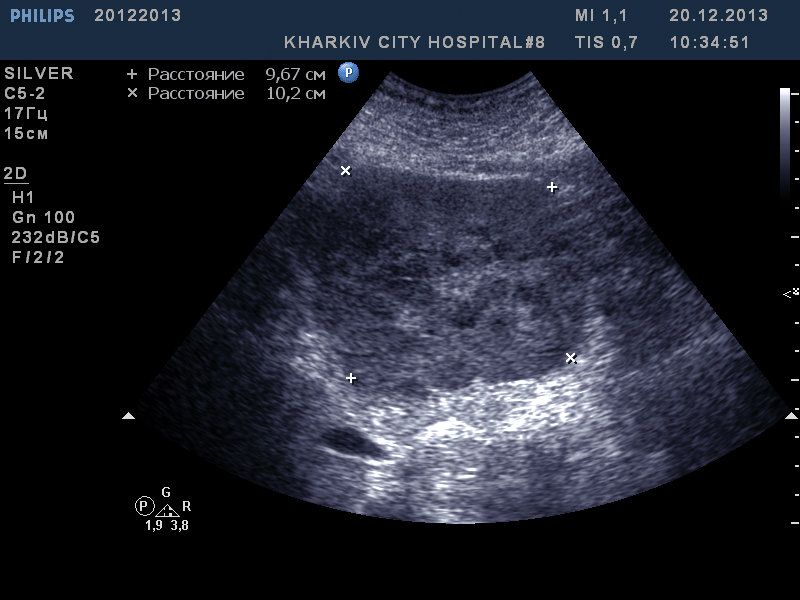

в эпигастрии в проекции левой доли данная картина. Ваши мнения?

аденокарцинома? очаговая узловая гиперплазия вряд ли